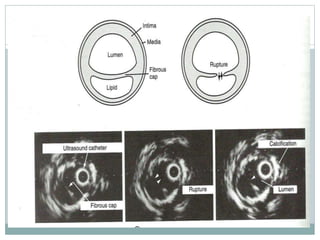

IVUS

IVUS to identify TCFAs

 Overestimates cap thicknessdue to poor axial resolution.

 Necroticcore: sensitivity of 46% and specificity of 97%. Looks as

a echolucentarea.

 Plaqueinflammation:detectionof macrophages not possible

due to poor resolution.

 Positiveremodelling: gold standard method.